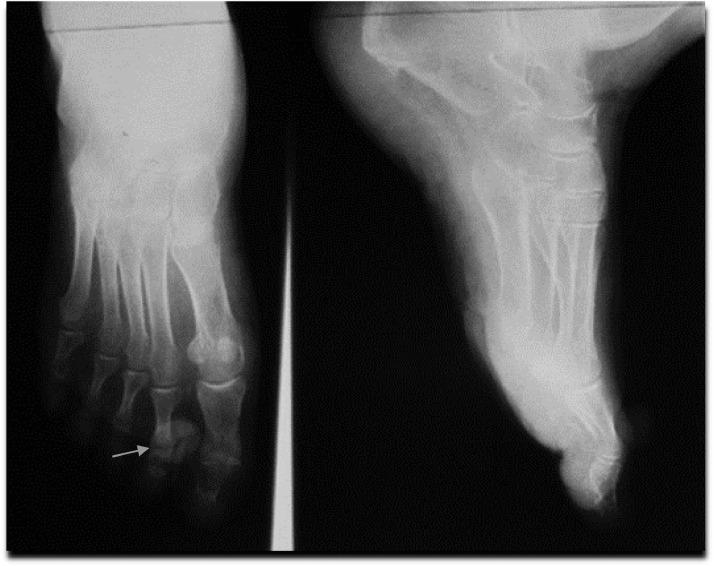

Eccrine poroma localized in the second toe.

小汗腺汗孔瘤位于第二趾。